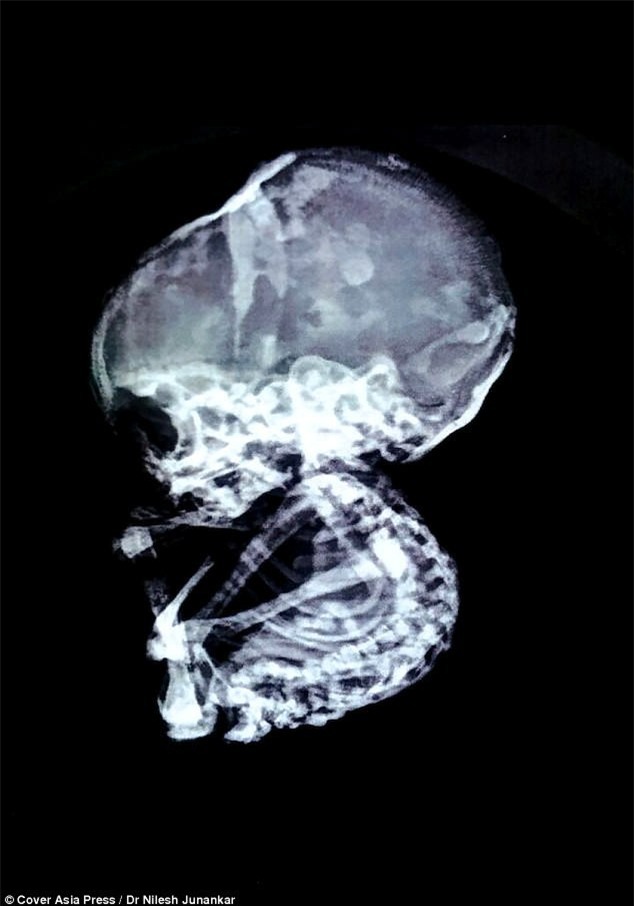

Khi đó bác sĩ phát hiện một "vật thể lạ" tắc nghẽn trong ruột, ngăn chặn hệ thống tiêu hóa. Tiến sĩ Nilesh Junankar, bác sỹ phẫu thuật nội soi, cho biết: "Qua kiểm tra, chúng tôi phát hiện vật thể giống như đá gây tắc nghẽn đường ruột, chặn đường ống thực phẩm của cô ấy".

Họ quyết định phẫu thuật gấp để lấy vật thể ra. Đến lúc này, tất cả các bác sĩ có mặt ở tại phòng mổ mới sốc nặng khi nhận ra rằng vật thể lạ đó chính là hình hài của một em bé.

Ca phẫu thuật kéo dài hơn 2 tiếng đồng hồ. Cuối cùng bác sĩ cũng lấy được bào thai hóa đá ra khỏi bụng bà mẹ.

Tiến sĩ Nilesh nói: "Đó là một cú sốc cho tất cả mọi người. Sau khi mở bụng bệnh nhân, chúng tôi bàng hoàng nhận ra đó là một đứa trẻ đã hóa đá. Điều kỳ lạ là đứa trẻ lại nằm ở phần bụng trên. Tử cung, buồng trứng và ống dẫn trứng của bệnh nhân hoàn toàn bình thường. Bệnh nhân đã mãn kinh sau 5 năm phá thai".

Điều đáng nói là vào thời điểm phá thai, bác sĩ khẳng định bào thai đã được đưa ra ngoài nhưng 15 năm sau đứa trẻ đã hình thành đủ các bộ phận cơ thể vẫn còn nằm trong bụng người phụ nữ.

Hiện tượng bào thai hóa

đá (hay còn gọi là Lithopedion) là vô cùng hiếm gặp, chỉ có khoảng 300

trường hợp từng được ghi nhận trong vòng 400 năm qua trên toàn thế giới.